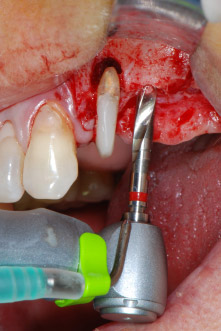

Implant beds were prepared at sites 25 and 26 with rotary instruments, used in a contra-angle handpiece with a 20 : 1 transmission ratio with an updated powerful implant motor (Implantmed, W&H) (Fig. 8).

The final preparation next to the sinus was again carried out with a piezoelectric instrument (Piezomed, insert S2).